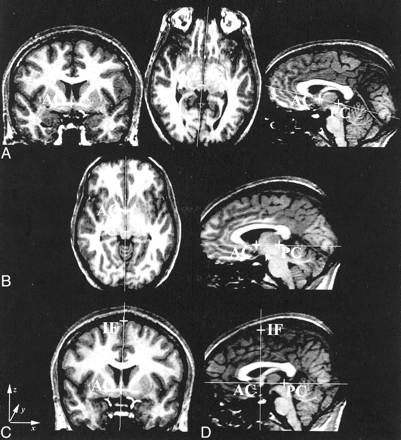

The brain data were reoriented in the image space (a cuboid) to account for variability in rotation, head tilt, and roll. The anterior commissure (AC) and posterior commissure (PC) were defined (with the aid of coronal and axial images) on the most anterior and superior images that contained their midline fibers (Fig 1A). The data were rotated about the PC until the AC-PC line was orthogonal to the faces of the image cuboid (Fig 1B), and resectioned by means of tri-linear interpolation but with no changes in scaling. (Tri-linear is the default; nearest-neighbor and sinc interpolations are also available.) The same AC was again chosen on the reformatted data. (MRreg displays the position of the original AC and PC interpolated onto the new dataset.) The interhemispheric fissure (IF) was defined on the same coronal image as the AC just below the superior sagittal sinus (Fig 1C). The data were rotated about the AC bringing the AC-IF line orthogonal to the faces of the image cuboid. The final reformatted image had the AC, PC, and IF in the midsagittal plane of the data cube (Fig 1D). We defined the midsagittal plane of the brain by using midpoints on the AC, PC, and IF. The CCA was then measured by means of manual tracing on the reconstructed image through this midsagittal plane.

Definition of the midsagittal plane. For the coronal images: x indicates left to right; y, posterior to anterior; and z, inferior to superior.

A, Coronal image through the AC (left), axial image through the PC (middle), and sagittal image of the AC-PC line before the first rotation (right).

B, AC-PC line orthogonal to the image cuboid.

C, Coronal image demonstrating the AC-IF line.

D, Sagittal image through the midsagittal plane after the final rotation.